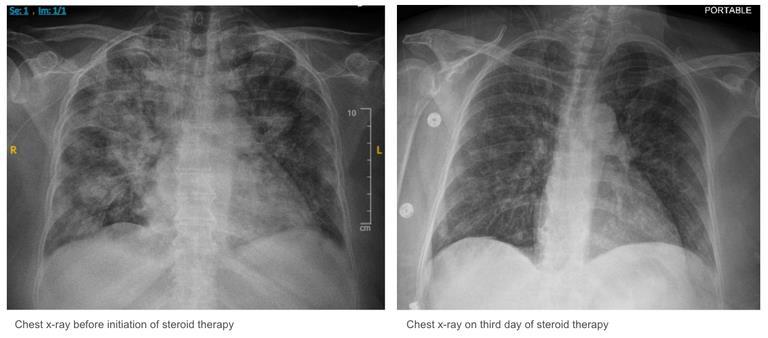

BACKGROUND/INTRODUCTION: The natural progression of interstitial lung disease in patients with dermatomyositis varies significantly. Some patients are asymptomatic or present with slowly progressive symptoms. A small minority of patients, however, present with an amyopathic (muscle-sparing) variant associated with rapidly progressive lung disease. This type of dermatomyositis is associated with the antimelanoma differentiation-associated gene 5 (MDA-5) autoantibody and is nearly uniformly fatal unless acted upon early and aggressively.

CASE PRESENTATION: We describe a case report of a 32-year-old male with no past medical history who presented to the hospital with a 2-month history of worsening dyspnea, cough, fatigue, involuntary weight loss, and myalgia. Prior to this presentation, he attended multiple emergency departments, urgent care, and outpatient visits for these symptoms. Hetested negative for COVID-19multiple times and initially treated for acute bronchitis and later for multifocal pneumonia during those encounters. His workup for pulmonary embolism was negative and computed tomography-chest showed diffuse patchy consolidations with lower lobe predominance. Pulmonary function tests demonstrated a restrictive pattern. The patient underwent extensive infectious and oncologic workup, all unrevealing. An initial myositis panel was negative. At the time of his exam with Rheumatology, a repeat myositis panel and skin biopsy were pending. On physical examination, the patient demonstrated diffuse inspiratory crackles bilaterally on auscultation, subtle violaceous plaques on his knees, and elbows, as well as nose, cheeks, and forehead. He had palmar erythema associated with fissuring and cracking of the skin of the palms, Gottron's papules on his fingers, and pronounced proximal muscular weakness characterized by limited neck flexion. Given the constellation of skin findings, myalgia, lung imaging, and rapidly progressive respiratory failure, a clinical diagnosis of melanoma differentiation-associated gene 5 (MDA5) dermatomyositis was made and later confirmed with a positive MDA5 test on the repeat myositis panel. Subsequently, he was aggressively treated with intravenous methylprednisolone, intravenous immunoglobulin (IVIG), and combination cyclophosphamide/tacrolimus therapy

CONCLUSION: Interstitial lung disease occurs in at least 30 percent of patients diagnosed with dermatomyositis. The presence of melanoma differentiation-associated gene 5 antibodies is linked to the elevated risk for interstitial lung disease progression, and for this reason, early recognition of cutaneous findings in the setting of myalgias and respiratory failure is crucial for early intervention and aggressive systemic treatment. This case report represents the importance of the physical examination for early diagnosis and management particularly relevant in the absence of available specific autoantibody tests.

34

ABSTRACT #11

CASE REPORT/CLINICAL REVIEW/CLINICAL VIGNETTE INFECTIOUS DISEASES

ELSBERG SYNDROME IN HSV-2 INFECTION

Omar Belfaqeeh1, Alexandria Markley1, Mudita Patel1,2, Brian Markoff1, Georgina Osorio1

1Mount Sinai Morningside-West Hospitals, Icahn School of Medicine at Mount Sinai, New York, NY, United States;

2Mount Sinai Beth Israel Hospital, Icahn School of Medicine at Mount Sinai, New York, NY, United States

Published in IDCases, 2023. PMID: 36875152

BACKGROUND/INTRODUCTION: Elsberg syndrome is a neuroinflammatory disease that causes acute or subacute lumbosacral radiculitis, with or without myelitis. Elsberg syndrome typically presents as cauda equina syndrome, with symptoms of sensory impairment, lower extremity weakness, saddle anesthesia, and urinary and/or bowel incontinence. It is usually associated with infectious causes such as SARS-CoV-2, West Nile Virus, Varicella Zoster Virus (VZV), and Herpes Simplex Virus Type 2 (HSV-2), with HSV-2 being the predominate causative pathogen. Treatment with acyclovir, even in cases without a definitive viral cause, is considered beneficial in many cases. Duration of treatment varies and is typically between 10 and 21 days. The use of steroids in the treatment of Elsberg syndrome is debated. Oral steroid tapers or short course high dose intravenous steroids can be used to help shorten the duration of symptoms. Elsberg syndrome accounts for approximately 5–10% of cauda equina syndrome and myelitis and up to 30% of patients have a recurrence of symptoms within the first year. Below we present a unique case of HSV-2 lumbosacral radiculitis (Elsberg Syndrome) diagnosed at a large New York City Hospital Center.

CASE PRESENTATION: Our patient was a 51-year-old female with a past medical history significant for fibromyalgia, right-sided sciatica, right lower extremity deep venous thrombosis, asthma, nephrolithiasis, vertigo, and oral and genital herpes infection who recently returned from Dominican Republic. She presented to the emergency room with complaints of a 10-day history of progressive lower extremity sensory changes and weakness preceded by transient bilateral arm pain and neck and head pressure. Furthermore, she reported being unable to completely void for one day in duration. She described the weakness to be worse in the right leg compared to the left leg, describing it as “leg heaviness” which resulted in a fall at home a day prior to presentation. While she was sitting in the bathroom, she tried to stand but her knees ’buckled’ and she fell backward, hitting her head on the floor (denied any loss of consciousness). Her family carried her to the Emergency Department as she was unable to bear weight. Vital signs on presentation were within normal limits. Physical exam was most notable for reduced power of knee flexors and knee extensors (3/5), dysesthesia to touch and pinprick from mid-thigh distally in stocking distribution bilaterally, absent knee reflexes bilaterally, positive Babinski sign bilaterally, and no clonus. Given her weakness and urinary hesitancy, a magnetic resonance imaging (MRI) of the cervical, thoracic, and lumbar spine was done to assess for spinal cord pathology and a bladder scan was done to rule out urinary retention. Neurology evaluated the patient for acute progressive lower extremity neuropathic pain and weakness. A lumbar puncture was performed to rule out atypical Guillain Barre syndrome or multiple sclerosis.

Complete blood count showed a white blood cell count of 5.1 ×103 cells/mL, hemoglobin of 11.9 g/dL, platelet count of 371 × 103 cells/ mL, and eosinophils elevated to 5.7%. The basic metabolic panel was within normal limits. Vitamin B12 level came back low at 290 pg/mL, homocysteine of 11.2, erythrocyte sedimentation rate of 30.9 and c-reactive protein of 5.9. Other labs including creatine phosphokinase, aldolase, methylmalonic acid, Lyme titers, copper level, vitamin B12, SSA/SSB (Sjogren Antibodies), were unremarkable. The cerebrospinal fluid PCR cytology showed pleocytosis with a WBC count of 360 (100% lymphocytes), although no albumin cytologic dissociation was seen, and protein of 182 mg/dL. Cerebrospinal fluid PCR was positive for HSV-2.

Infectious disease was consulted and reviewed the MRI of the spine with radiology, which demonstrated a very faint enhancement of the L4–5 nerve roots. An MRI of the brain came back within normal limits. An initial

35